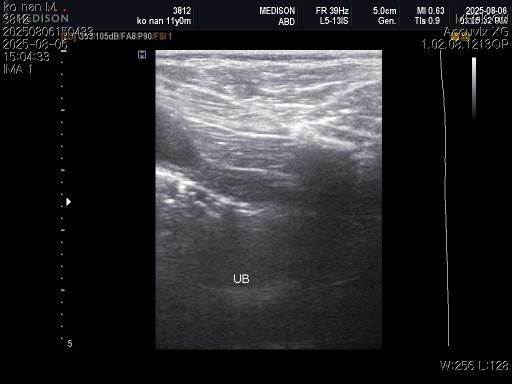

강아지 혈뇨의 원인을 찾고 있습니다 저희 강아지 두번도 아니고 딱 한번만 살려주세요..

1) 혈액검사와 엑스레이 그리고 초음파상 혈뇨의 원인이 나타나지가 않는지 궁금합니다.

2) 그리고 전립선 비대가 있는지도 없는지 여부가 궁금합니다.

3) 신장결석이 어느정도인지도 궁금합니다.